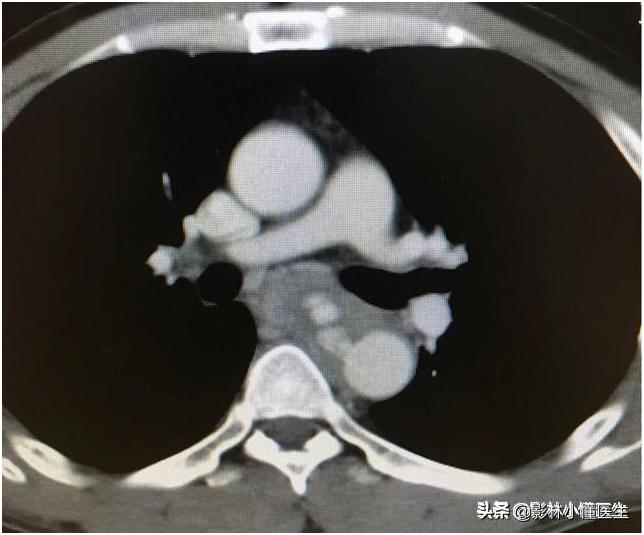

例2

鱼刺刺穿食管及主动脉壁,治疗费用高、预后极差。